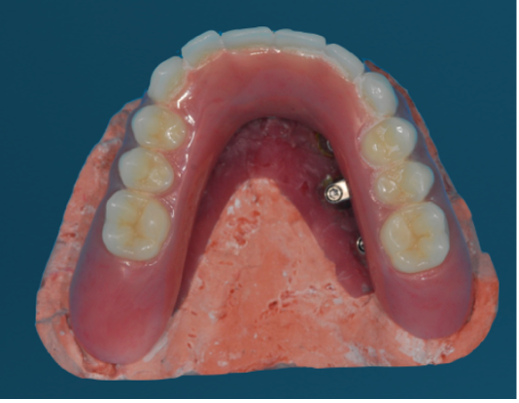

Patient Factors that May Contraindicate Fixed Implant-supported Prosthetics

(42.) Fixed-removable prosthesis.

Figure 42

(43.) Fixed-removable prosthesis.

Figure 43